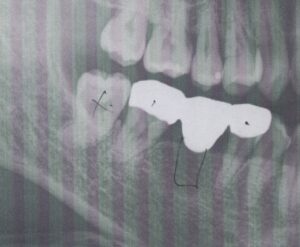

前歯が噛んでいない

治療方針

右下567のブリッジは構造力学的に問題が多いです。簡単言うと、噛む力に耐えられません。

上顎であればいいのですが、下顎の場合、骨が撓まない・歯が短いといった理由からです。

そのため、現在では下6が抜歯になれば、インプラントが第一選択肢となります。

また、奥歯を治療する際には、前歯がきちんと噛んでいることが条件となります。